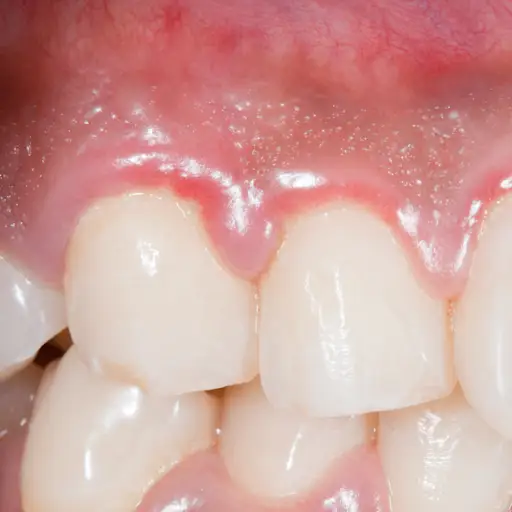

红色,肿胀,嫩牙龈

患有糖尿病的人更容易有口香糖疾病。症状包括红色,肿胀和嫩牙龈。当葡萄糖水平因糖尿病而上升时,唾液中的糖水平增加。糖喂嘴里的细菌。食物与细菌和食物结合形成斑块,这是一种可引起牙龈疾病,蛀牙和口臭的粘性薄膜。

反过来,牙龈疾病会导致炎症,这也增加了葡萄糖水平,使得糖尿病更难。好消息是治疗牙龈疾病实际上可以随时间降低葡萄糖水平。